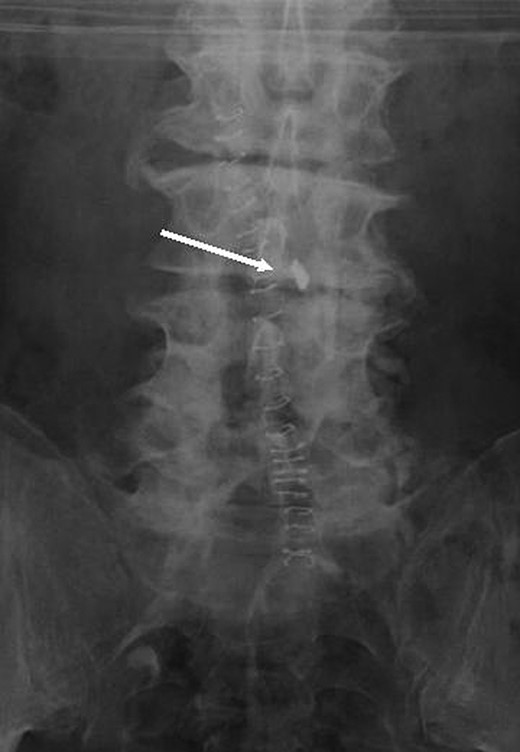

Postoperative Anterior-Posterior and lateral (Figs 1 and 2) radiographs of the lumbo-sacral spine revealed a radio-opaque foreign body on the right side of the spinal canal. The patient returned to theatre 3 days following the original operation for wound exploration. The foreign body was found to be lying in the spinal canal on the right side with an associated small dural tear. The object was identified as a broken metal tip and traced to an osteotome used in the primary procedure.

The most plausible explanation for this complication is that during the release of the hypertrophied facet joint, the osteotome tip broke. What is particularly concerning is the fact that although the approach was on the left side, the broken tip was able to traverse the midline and settle adjacent to the spinal canal on the right, tearing the dura in the process.